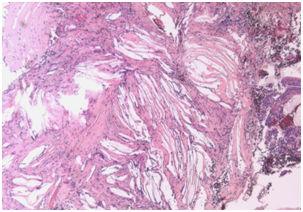

Final diagnosis: The histopathological analysis confirmed the suspicion of cholesterol granuloma and demonstrated abundant cholesterol clefts with giant cells around them and inflammatory cells (Figure 3).

Figure 3 Cholesterol clefts with giant cells around them and inflammatory cells.